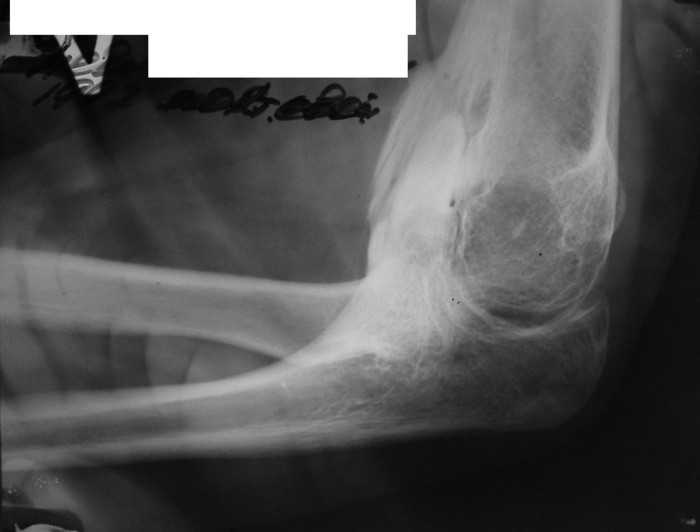

Вложение не в текстовом формате было извлечено…

Имя     : elbow07.JPG